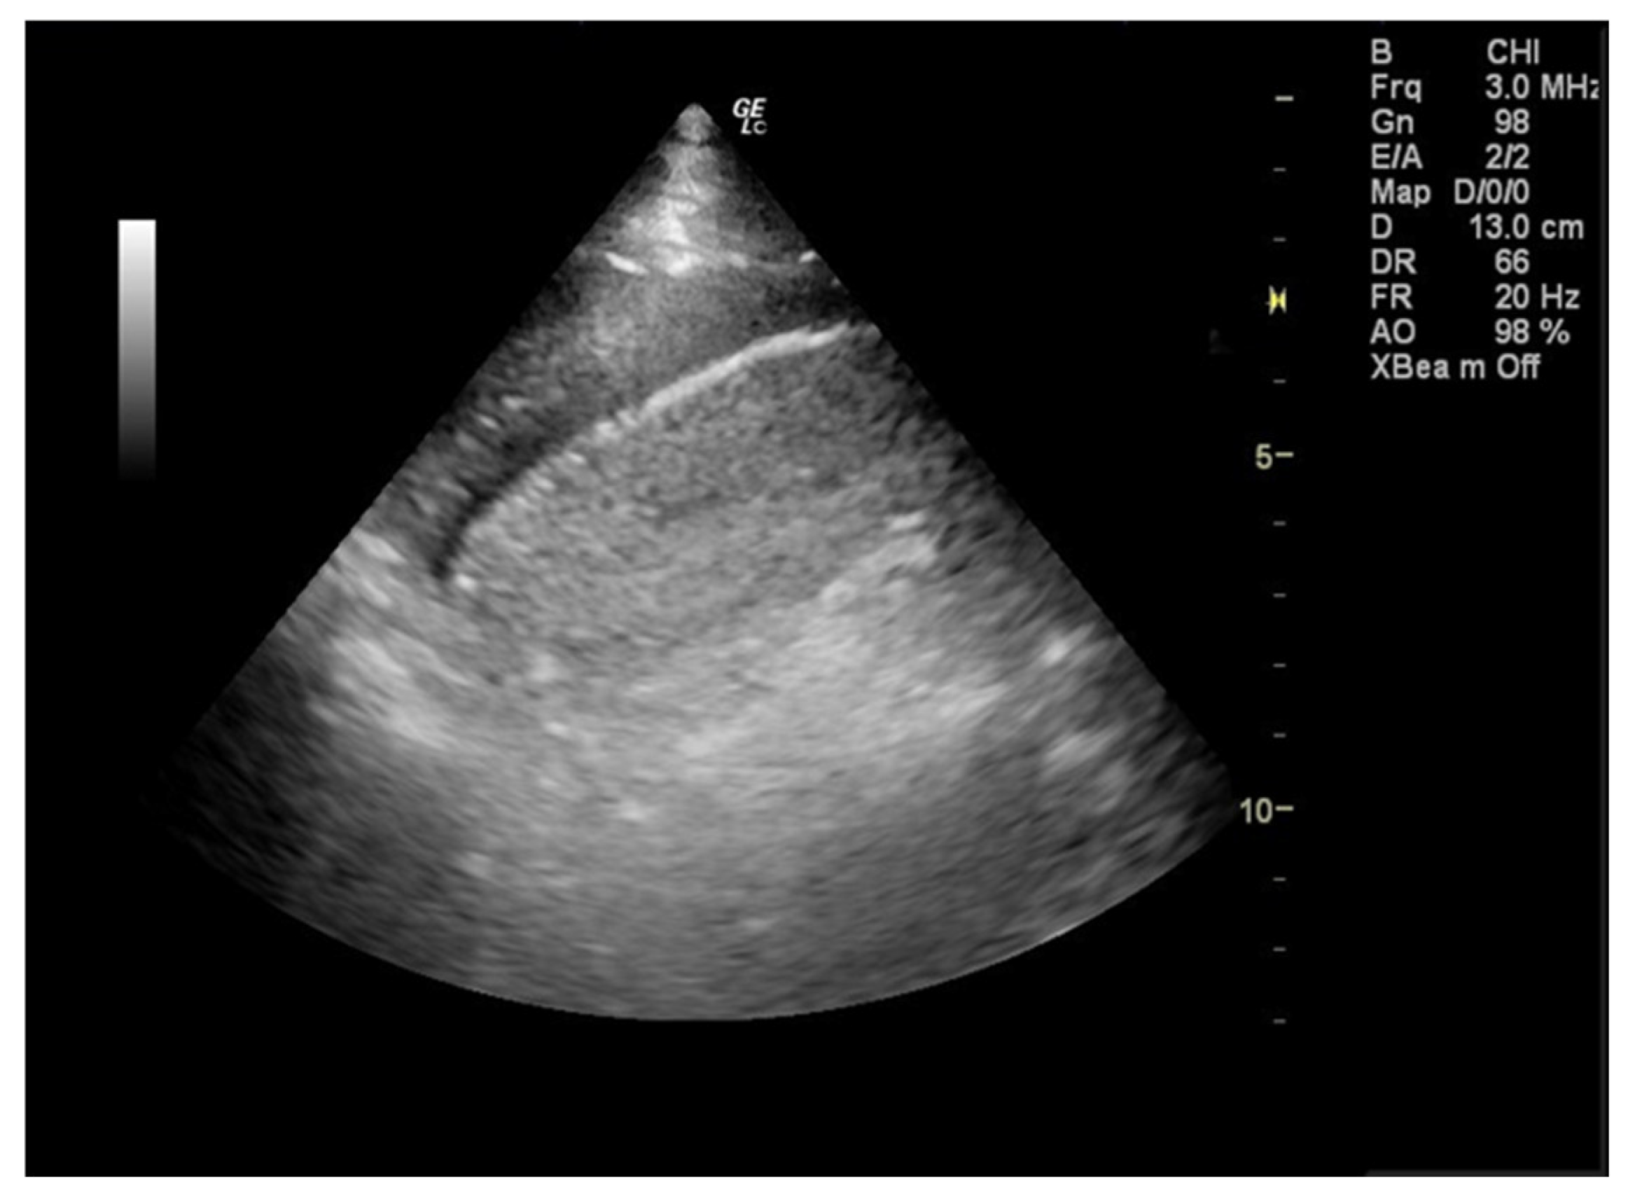

During her stay in the emergency department the 12-lead electrocardiogram showed normal sinus rhythm and the cardiac ultrasound was without any pathological findings. A focused lung ultrasound was conducted without the presence of B-lines, but a small anechoic left pleural effusion was discovered when placing the transducer in the left posterior axillary line at the lower part of the chest (Figure 1). Due to the left sharp “shingles-like” pain and the pleural effusion that was found, an abdomen ultrasound was performed in order to investigate possible abdominal pathology, which was unremarkable. According to the Wells Criteria for Pulmonary Embolism, she was a moderate risk patient for pulmonary embolism. Due to the absence of any other obvious cause of the pleural pain and the pleural effusion, a computed tomography pulmonary angiography (CTPa) was conducted. The CTPa scan was negative for pulmonary embolism, but verified the aforementioned left pleural effusion. The CTPa did not show any other significant findings from the pulmonary parenchyma or the mediastinum, besides a large diaphragmatic hernia already known about (Figure 2).

Figure 1.

During the focused lung ultrasound a small left pleural effusion was detected by placing the transducer in the left posterior axillary line at the lower part of the chest (zone L3).